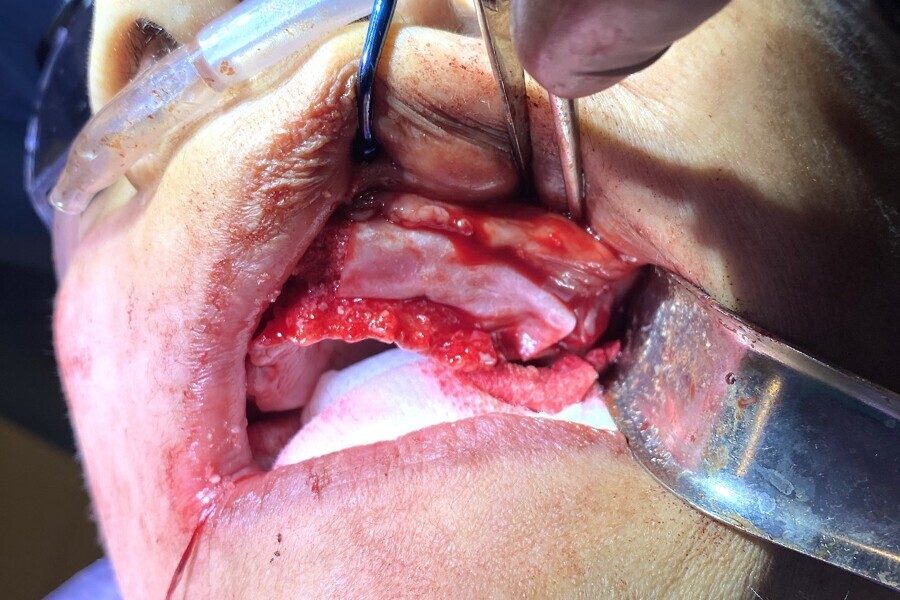

A full-thickness mucoperiosteal flap was elevated from the approximate areas of tooth #46 to tooth #35 and carefully reflected to expose the alveolar ridge. A bone reduction guide was placed over the site and fixated with four anchor pins. The bone was then reduced to the planned vertical height with rongeurs and flattened with carbide burs in a straight handpiece (Alveoplasty Kit, Meisinger USA). Based upon the 3D planning, the 3D-printed osteotomy drilling guide was designed to fit over the reduced bone and fixated in the same holes as the bone reduction guide (Fig. 13). The fixation pins were of two different lengths and secured the resin guide to the mandible (Fixation Kit, ROE Dental Laboratory). The osteotomies were prepared with sequential guided drills for accuracy, and five implants (Helix Grand Morse, Neodent) were placed approximately 2 mm subcrestally (Fig. 14). Although the implants all exhibited moderate insertion torque, the intermedullary bone density within the mandibular implant receptor sites was poor, as previously noted during the diagnostic phase.

Each implant was then objectively tested for stability using resonance frequency analysis, and implant stability quotient (ISQ) values were recorded (Osstell IDx, Osstell). The ISQ values confirmed the initial CBCT assessment of the mandibular bone, and a decision was made to bury the implants and leave them covered for approximately 2–3 months to provide sufficient opportunity and time for the implants to fully integrate within the mandibular bone prior to loading. Each subcrestally placed implant received a 2 mm cap screw to fill the coronal osteotomy site. All the residual tooth sockets and any defects or concave areas were then filled with the dentine grafting material (Fig. 15). Two 20 × 30 mm collagen membranes (MaxxMem, Community Tissue Services) were then draped over the grafted site and stabilised with deep horizontal mattress sutures. Closure was then achieved with continuous and interrupted sutures using #4/0 thread (VICRYL, Ethicon).